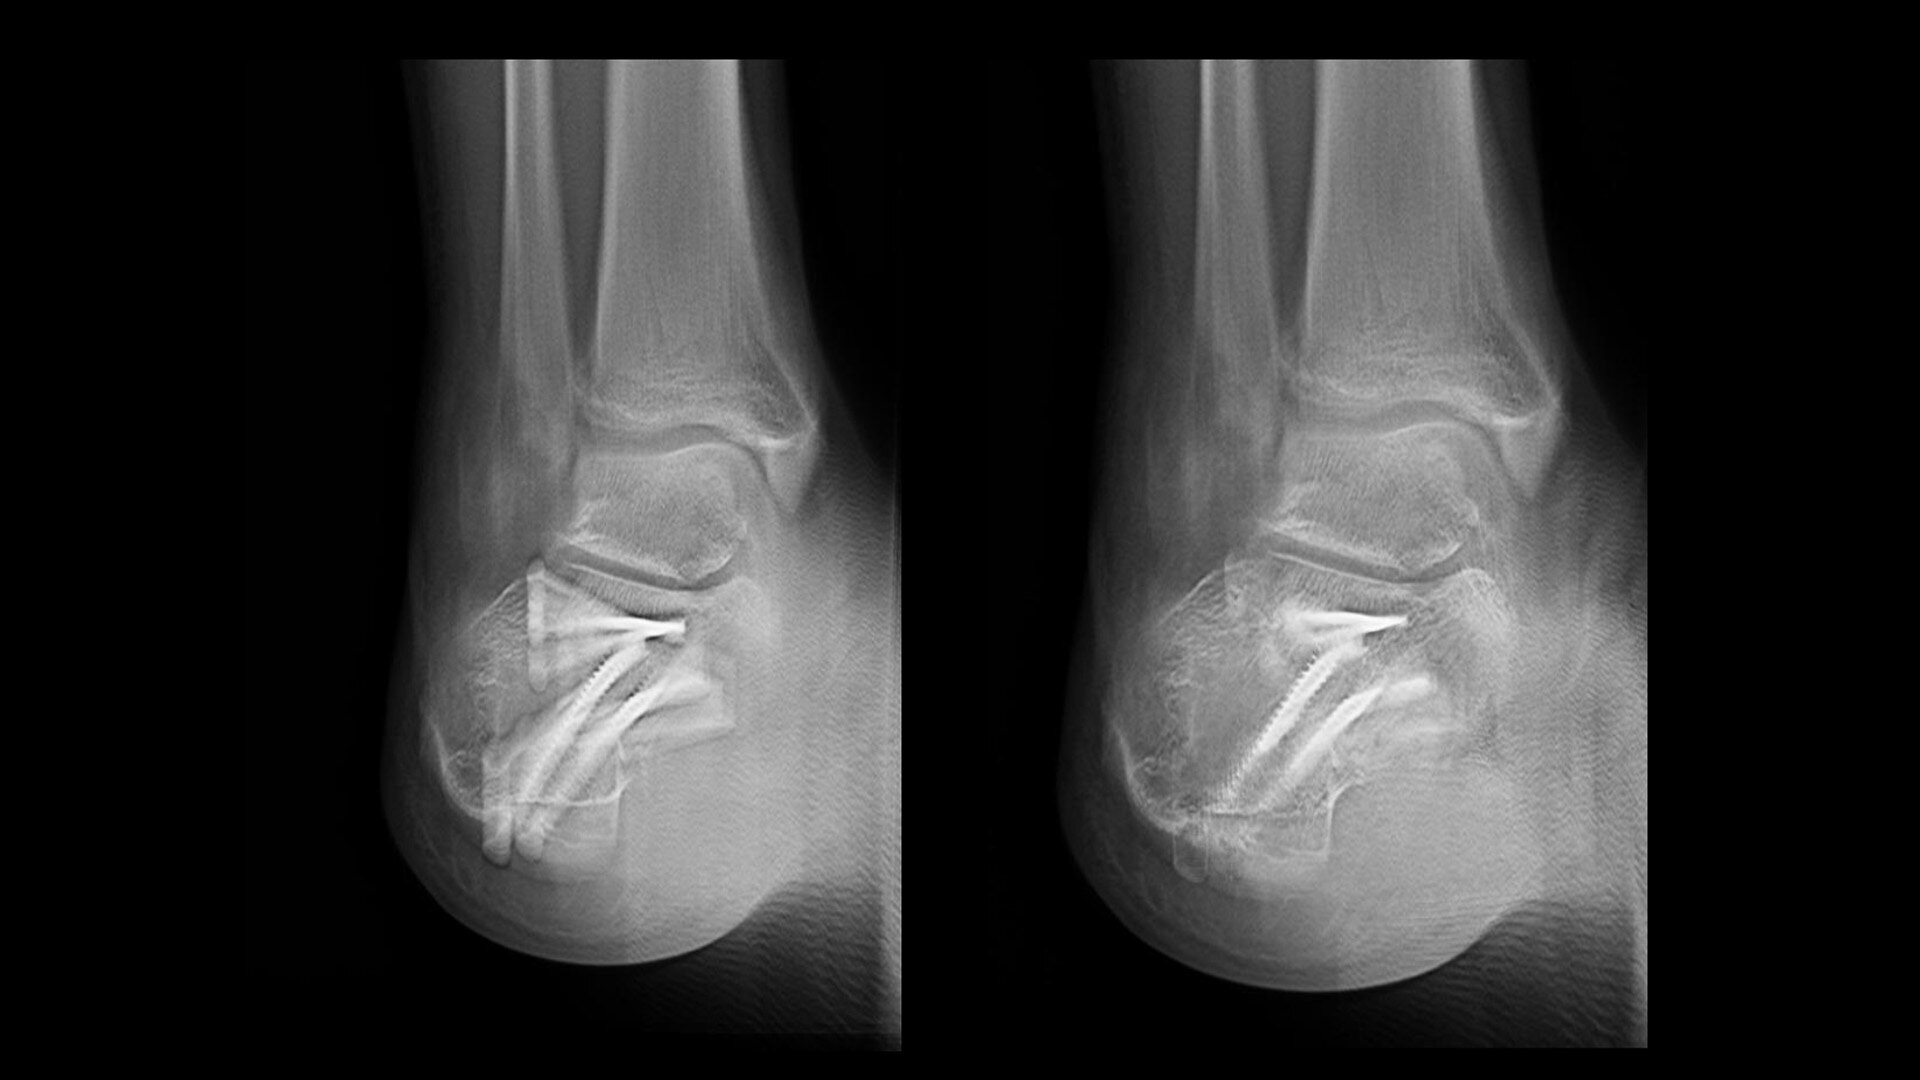

VolumeRAD Metal Artifact Reduction (MAR) provides quality multi-level image slices even with metal implants

Metallic implants often cause difficulty in digital tomographic imaging. Often black lines appear in the X-ray (an undershoot) or a white ring appears around the metal or there is streaking throughout the image. VolumeRAD Metal Artifact Reduction removes these effects, improving visibility, enabling analysis of implant placements and increasing clinical confidence.

Image caption: Wrist fracture with metal implant | Conventional (left) vs. VolumeRAD with Metal Artifact Reduction (right)